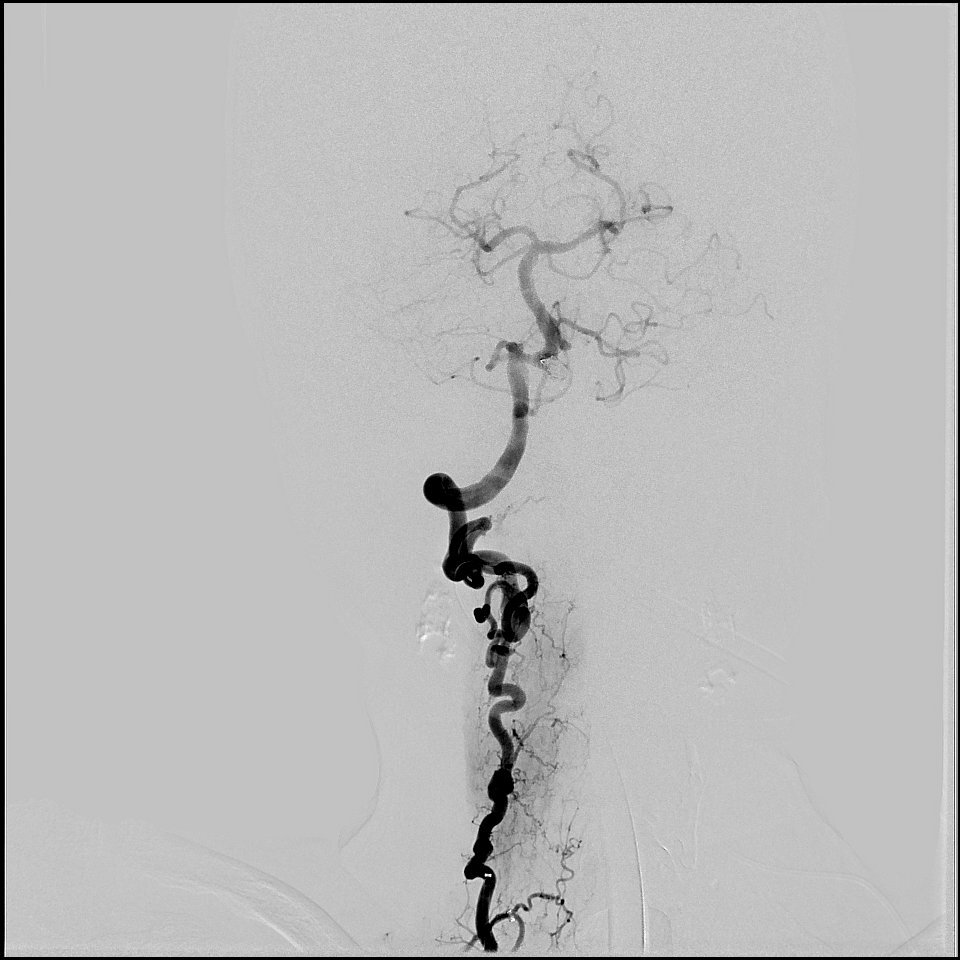

Balloon guide catheters for endovascular thrombectomy in patients with acute ischaemic stroke due to large-vessel occlusion in China (PROTECT-MT): a multicentre, open-label, blinded-endpoint, randomised controlled trial - The Lancet thelancet.com/journals/lance…

Is EVT better than MM for treating isolated PCA #strokes? 🤔Find out in our latest study published in the European Stroke Journal. Huge thanks to Dr. Benjamin Pulli, @vsyedavalli, @AdamDmytriw & @GuenegoAdrien for leading this important work! 🙌 journals.sagepub.com/doi/10.1177/23…

Is MT better than IVT for treating DMVO #strokes? 🤔 Find out in our latest study published in the Journal of Stroke (JoS). Huge thanks to @AdamDmytriw, @GuenegoAdrien, and @vsyedavalli for leading this important work! 🙌 Read the full paper here: j-stroke.org/journal/view.p…

🧠💉Pretreatment predictors of very poor clinical outcomes in medium vessel occlusion stroke patients treated with mechanical thrombectomy Very poor outcomes predicted by: ⏲️Advanced age, 📈Higher NIHSS scores, 📋Elevated pre-stroke mRS, 🩸Pre-operative glucose levels journals.sagepub.com/doi/full/10.11…